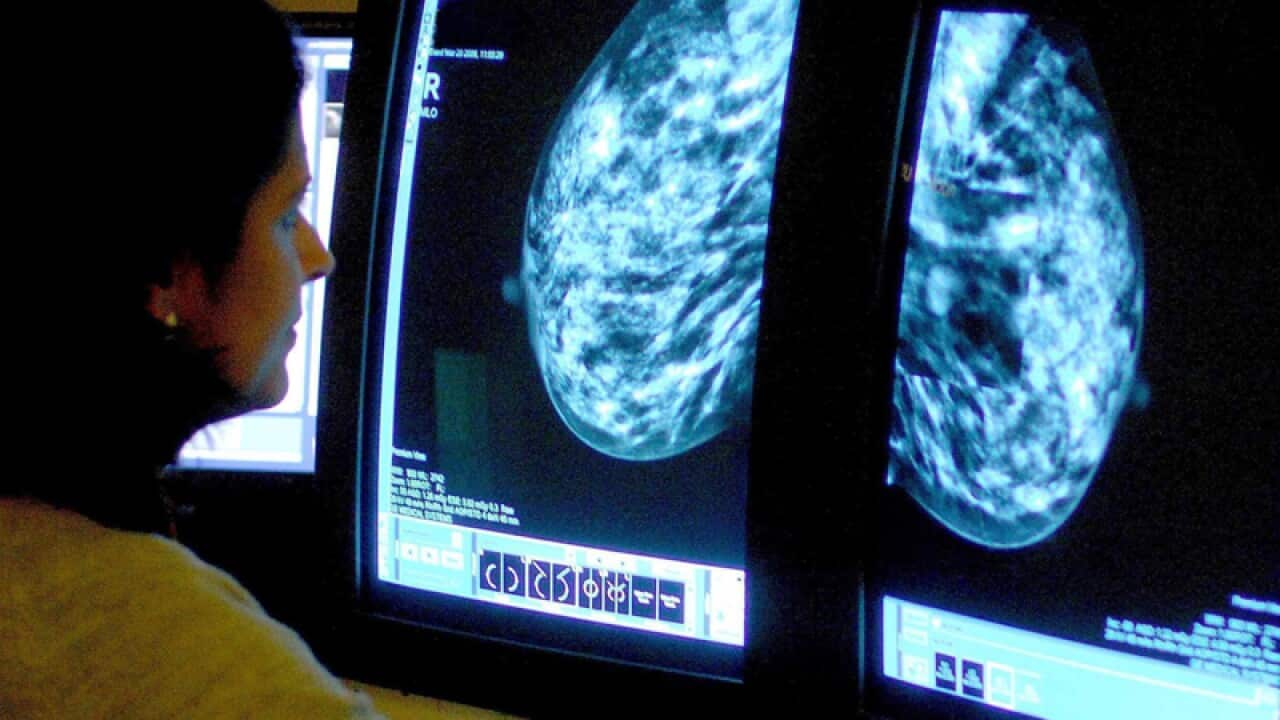

Australian scientists have made a discovery that could lead to a simple blood test with the potential to conquer treatment-resistant breast cancer.

The breakthrough relates to the most common form of the disease, oestrogen-receptor positive breast cancer.